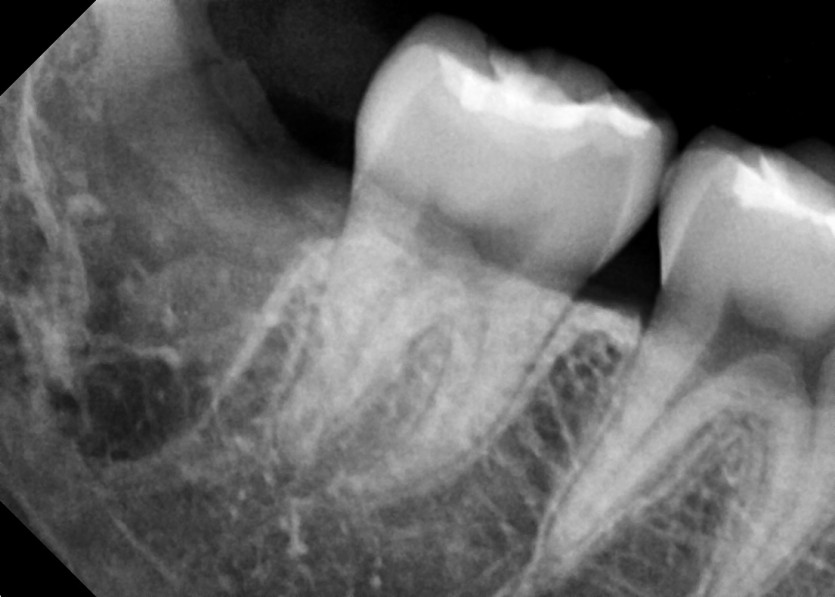

#18,48 사랑니 발치

구강 외과 전문의가 당일 발치했습니다.